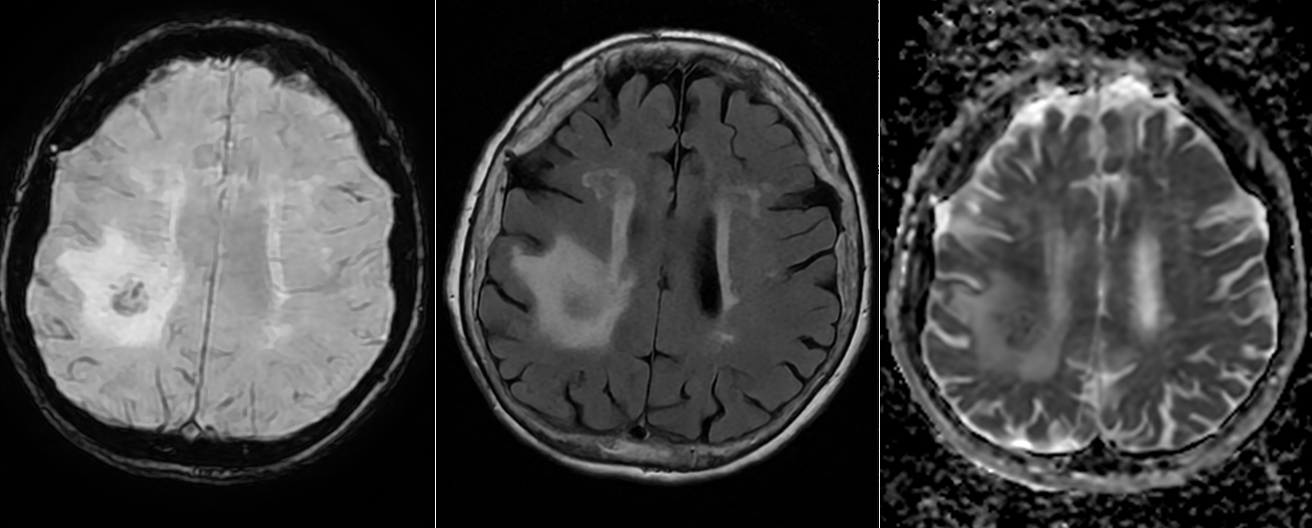

IRM cerebral cu substanță de contrast – metoda de elecție. Limfoamele sunt leziuni cu hipersemnal T2-FLAIR și hiposemnal T1, imprecis delimitate, cu contrast intens, adesea periventriculare si cu aspect caracteristic de difuzie (ADC). Poate mima glioblastomul sau metastazele cerebrale.